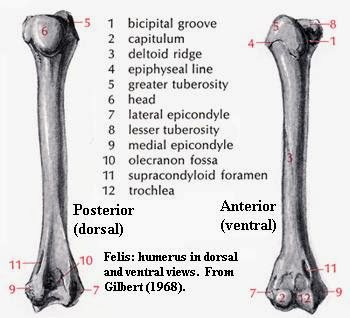

股骨 Femur 小小整理網站smallcollation

肱骨 Humerus 小小整理網站smallcollation

肱骨 Humerus 小小整理網站smallcollation

肱骨 Wikiwand

肱骨 肱骨 位於上臂 又叫上臂骨 上端有半球形的肱骨頭與肩胛骨的關節盂組 百科知識中文網

肱骨 维基百科 自由的百科全书